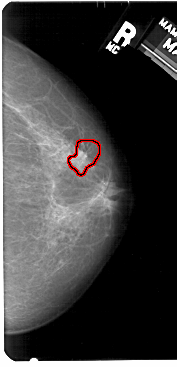

A_1520_1.LEFT_MLO

LEFT_MLO LINES 5491 PIXELS_PER_LINE 2716 BITS_PER_PIXEL 12 RESOLUTION 43.5 NON_OVERLAY

FILE: A_1520_1.RIGHT_MLO.OVERLAY

TOTAL_ABNORMALITIES 1

ABNORMALITY 1

LESION_TYPE CALCIFICATION TYPE PLEOMORPHIC DISTRIBUTION CLUSTERED

LESION_TYPE MASS SHAPE IRREGULAR MARGINS SPICULATED

ASSESSMENT 4

SUBTLETY 3

PATHOLOGY MALIGNANT

TOTAL_OUTLINES 1

BOUNDARY